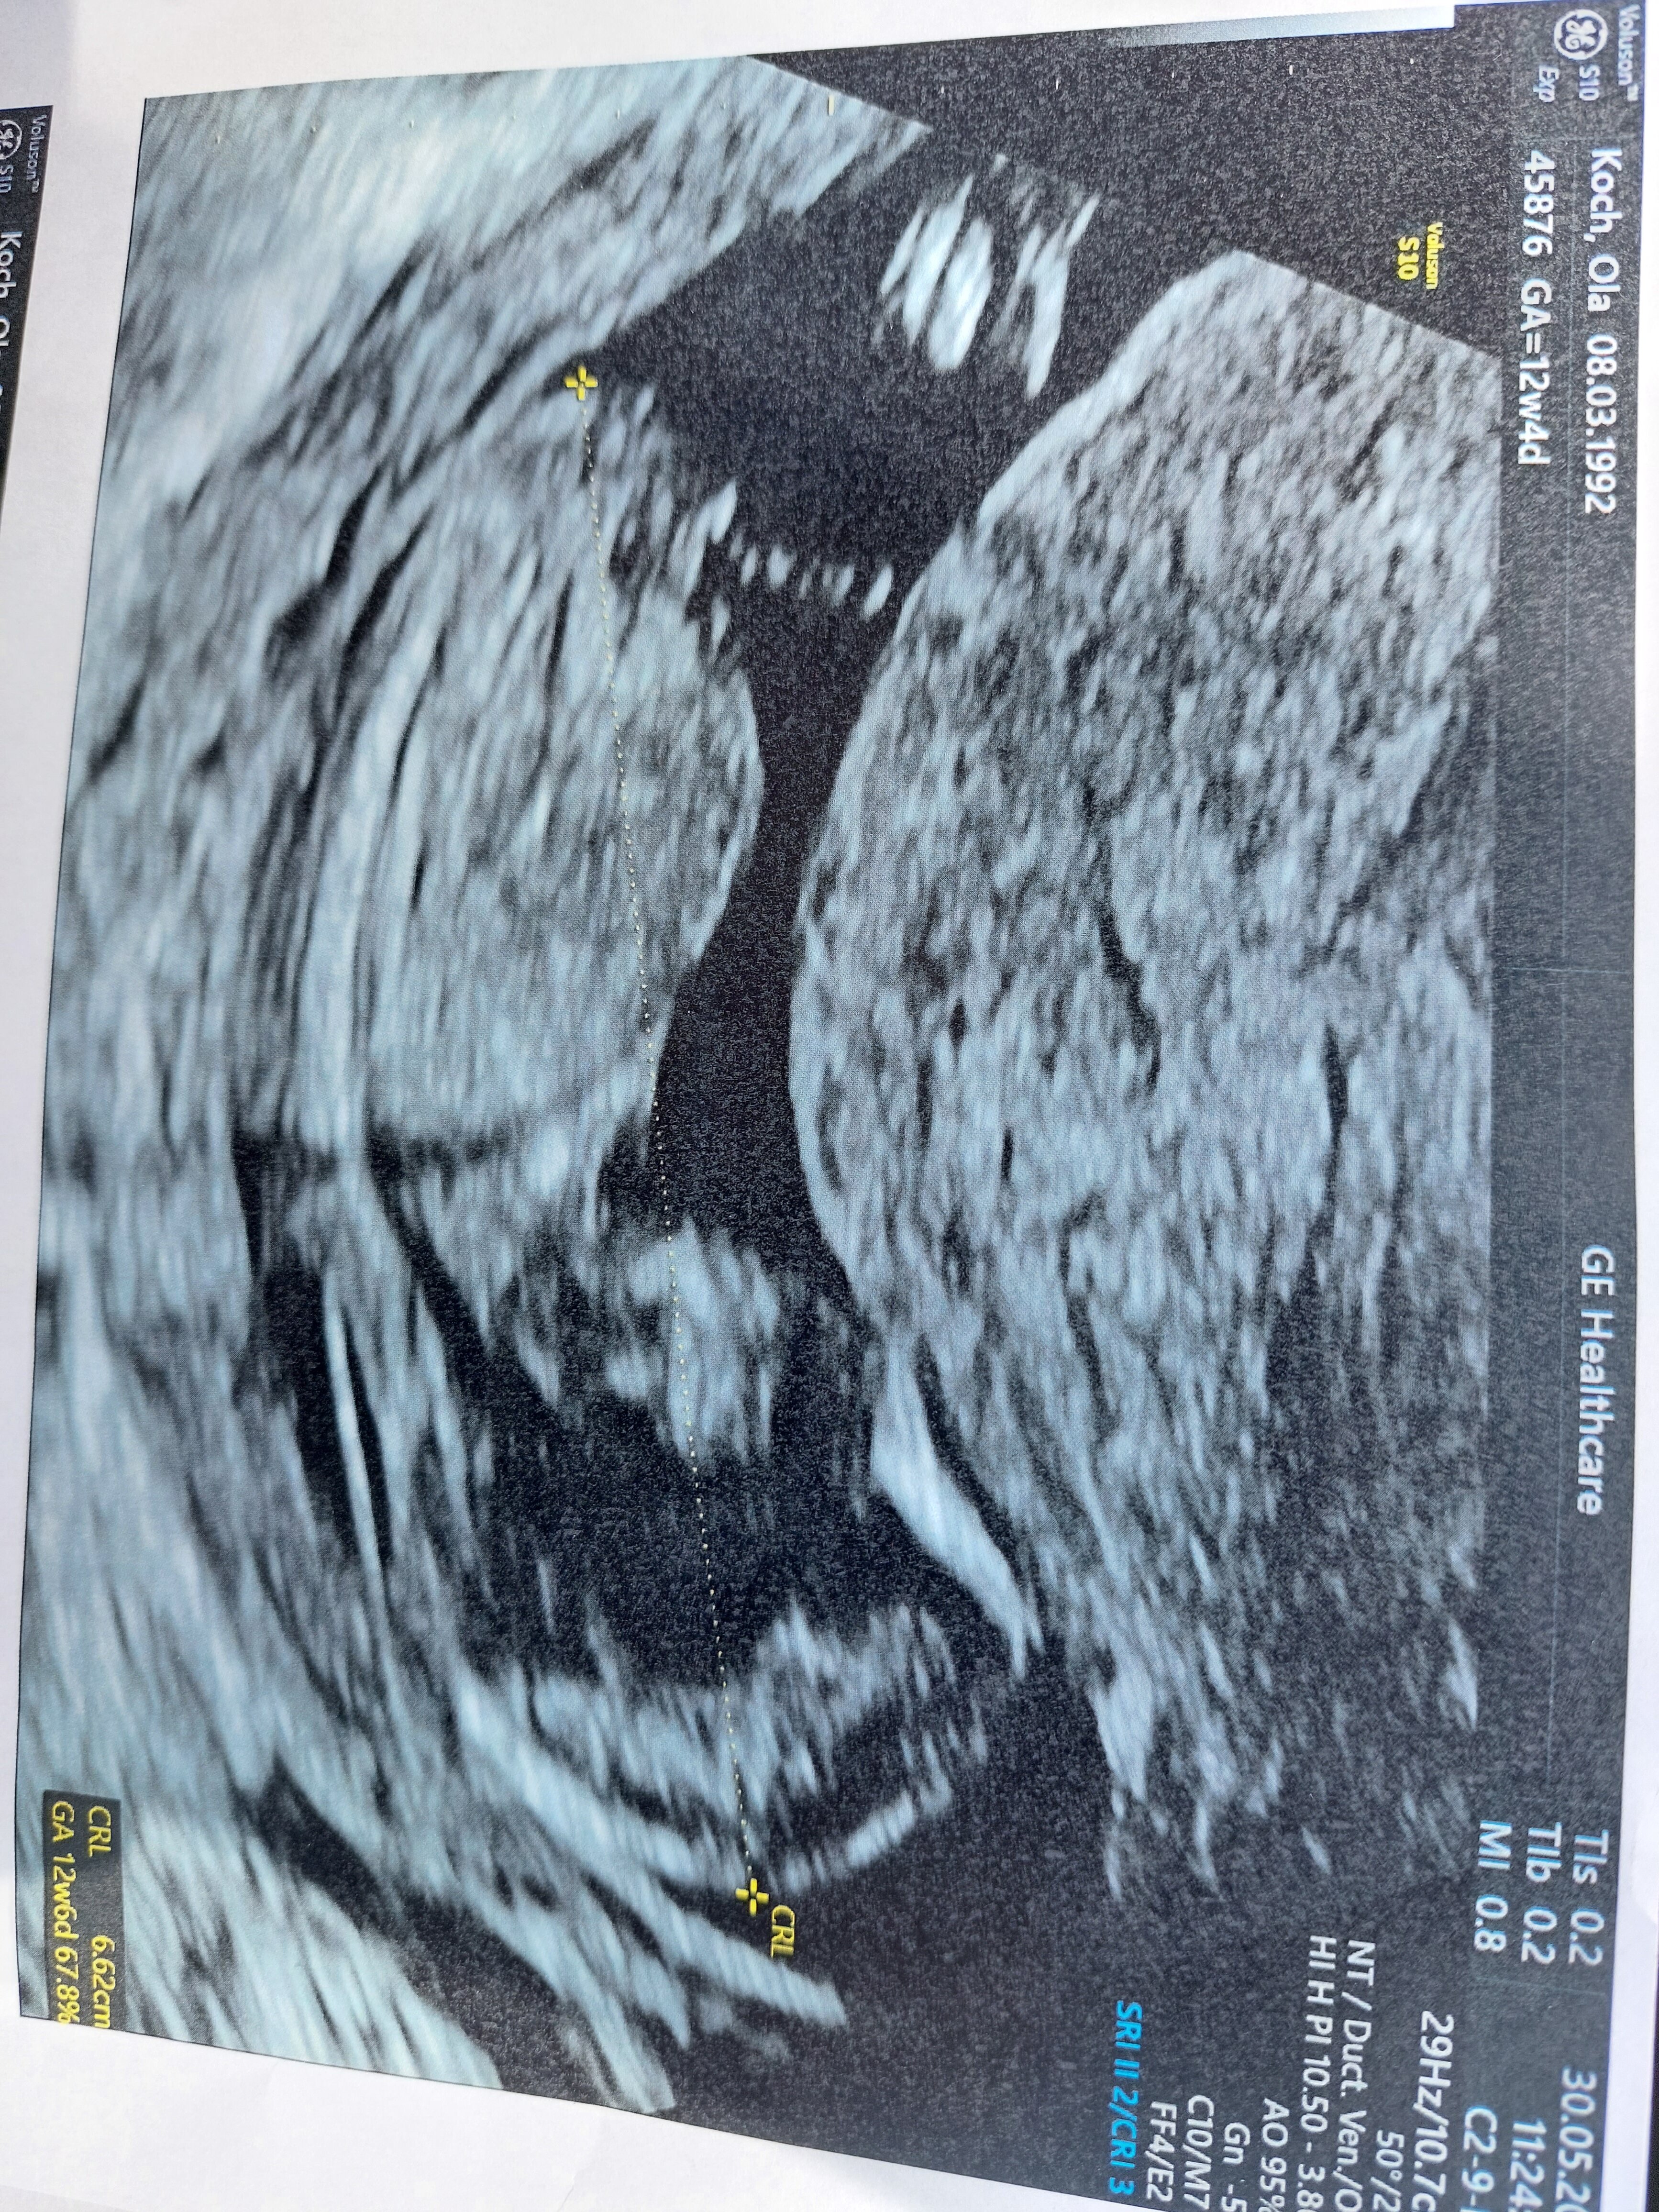

No i właśnie o tym mówiłam że względem kręgosłupa 😊 widziałam właśnie te zdjęcie i na tym się wzorowałam co do swojego też USG dziejszego ale kompletnie nie mam pojęcia co u mojej dzidzi widać bo lekarz mówił że zasłania się pępowiną 🙈😅 co wróżysz Kochana mi tutaj? 😄

• 20220530_120439.jpg

20220530_120439.jpg